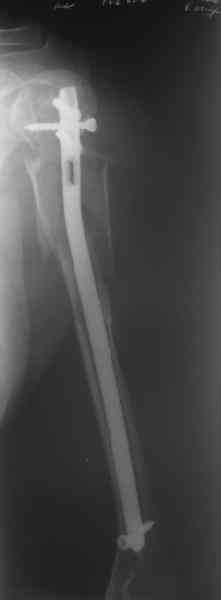

Здесь нет необходимости в серкляже. Вмешиваться на промежуточных отломках приходится, если есть угроза перфорации кожи, или промежуточный отломок попал в фасцию, как пуговица в петлю. В приложении сегментарный оскольчатый перелом плеча в проксимальном отделе, фиксированный больщеберцовым стержнем. Как видите, обошлось без серкляжа. Функция полная.

Это укороченный большеберцовый стержень, которые делает предприятие "ЦИТО".

Доступные на тот момент гвозди для плеча имели худшие возможности фиксации в коротком проксимальном отломке.